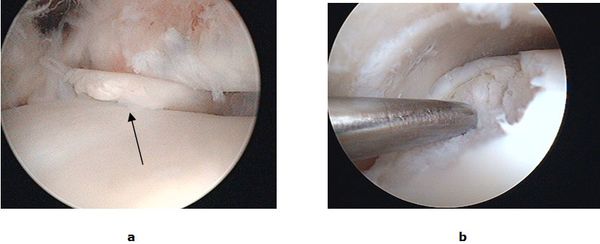

Bei isolierten Knorpel/Knochen Verletzungen (Osteochondrale Läsion, Osteochondrosis dissecans) kann während einer Gelenkspiegelung eine vitalisierende Anbohrung des Knochens erfolgen. Besteht bereits ein ausgeprägter Knorpelschaden wird mit einem speziellen Instrumentarium die harte Knochenschicht durchbrochen und die Bildung von Ersatzknorpel angeregt (Mikrofrakturierung). Der freie Gelenkkörper wird vorher entfernt. Dauerhaft schmerzhafte umschriebene Knorpelläsionen können durch die Verpflanzung eines Knorpel-Knochen-Zylinder (Mosaikplastik, Knorpel-Knochen-Zylinder Transplantation) therapiert werden. Aus einem gesunden nicht belasteten Gelenkanteil wird ein Knorpel-Knochen Zylinder entnommen und in der sog. „Press fit“ Technik am Sprungbein eingesetzt. Ein anderes Verfahren, die sog. MACT eignet sich zur Therapie großer Defektzonen. Bei der MACT (Matrix gekoppelte Autologe Chondrozyten Transplantation) wird Knorpel entnommen und an ein Speziallabor geschickt. Die entscheidenden Zellen werden isoliert, vermehrt und in einer Zweitoperation auf den Knorpeldefekt aufgebracht.

Abb.3: a Gelenkspiegelung mit freiem Gelenkkörper im oberen Sprunggelenk (OSG). b Mikrofrakturierung eines Knorpelulcus am Sprungbein.